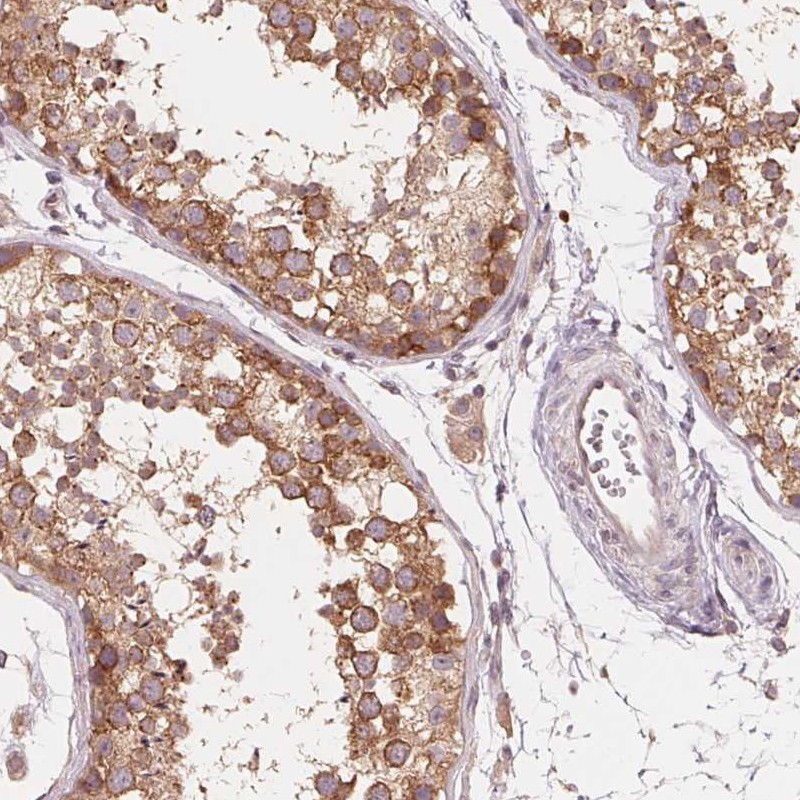

Immunohistochemical staining of human testis shows cytoplasmic positivity.